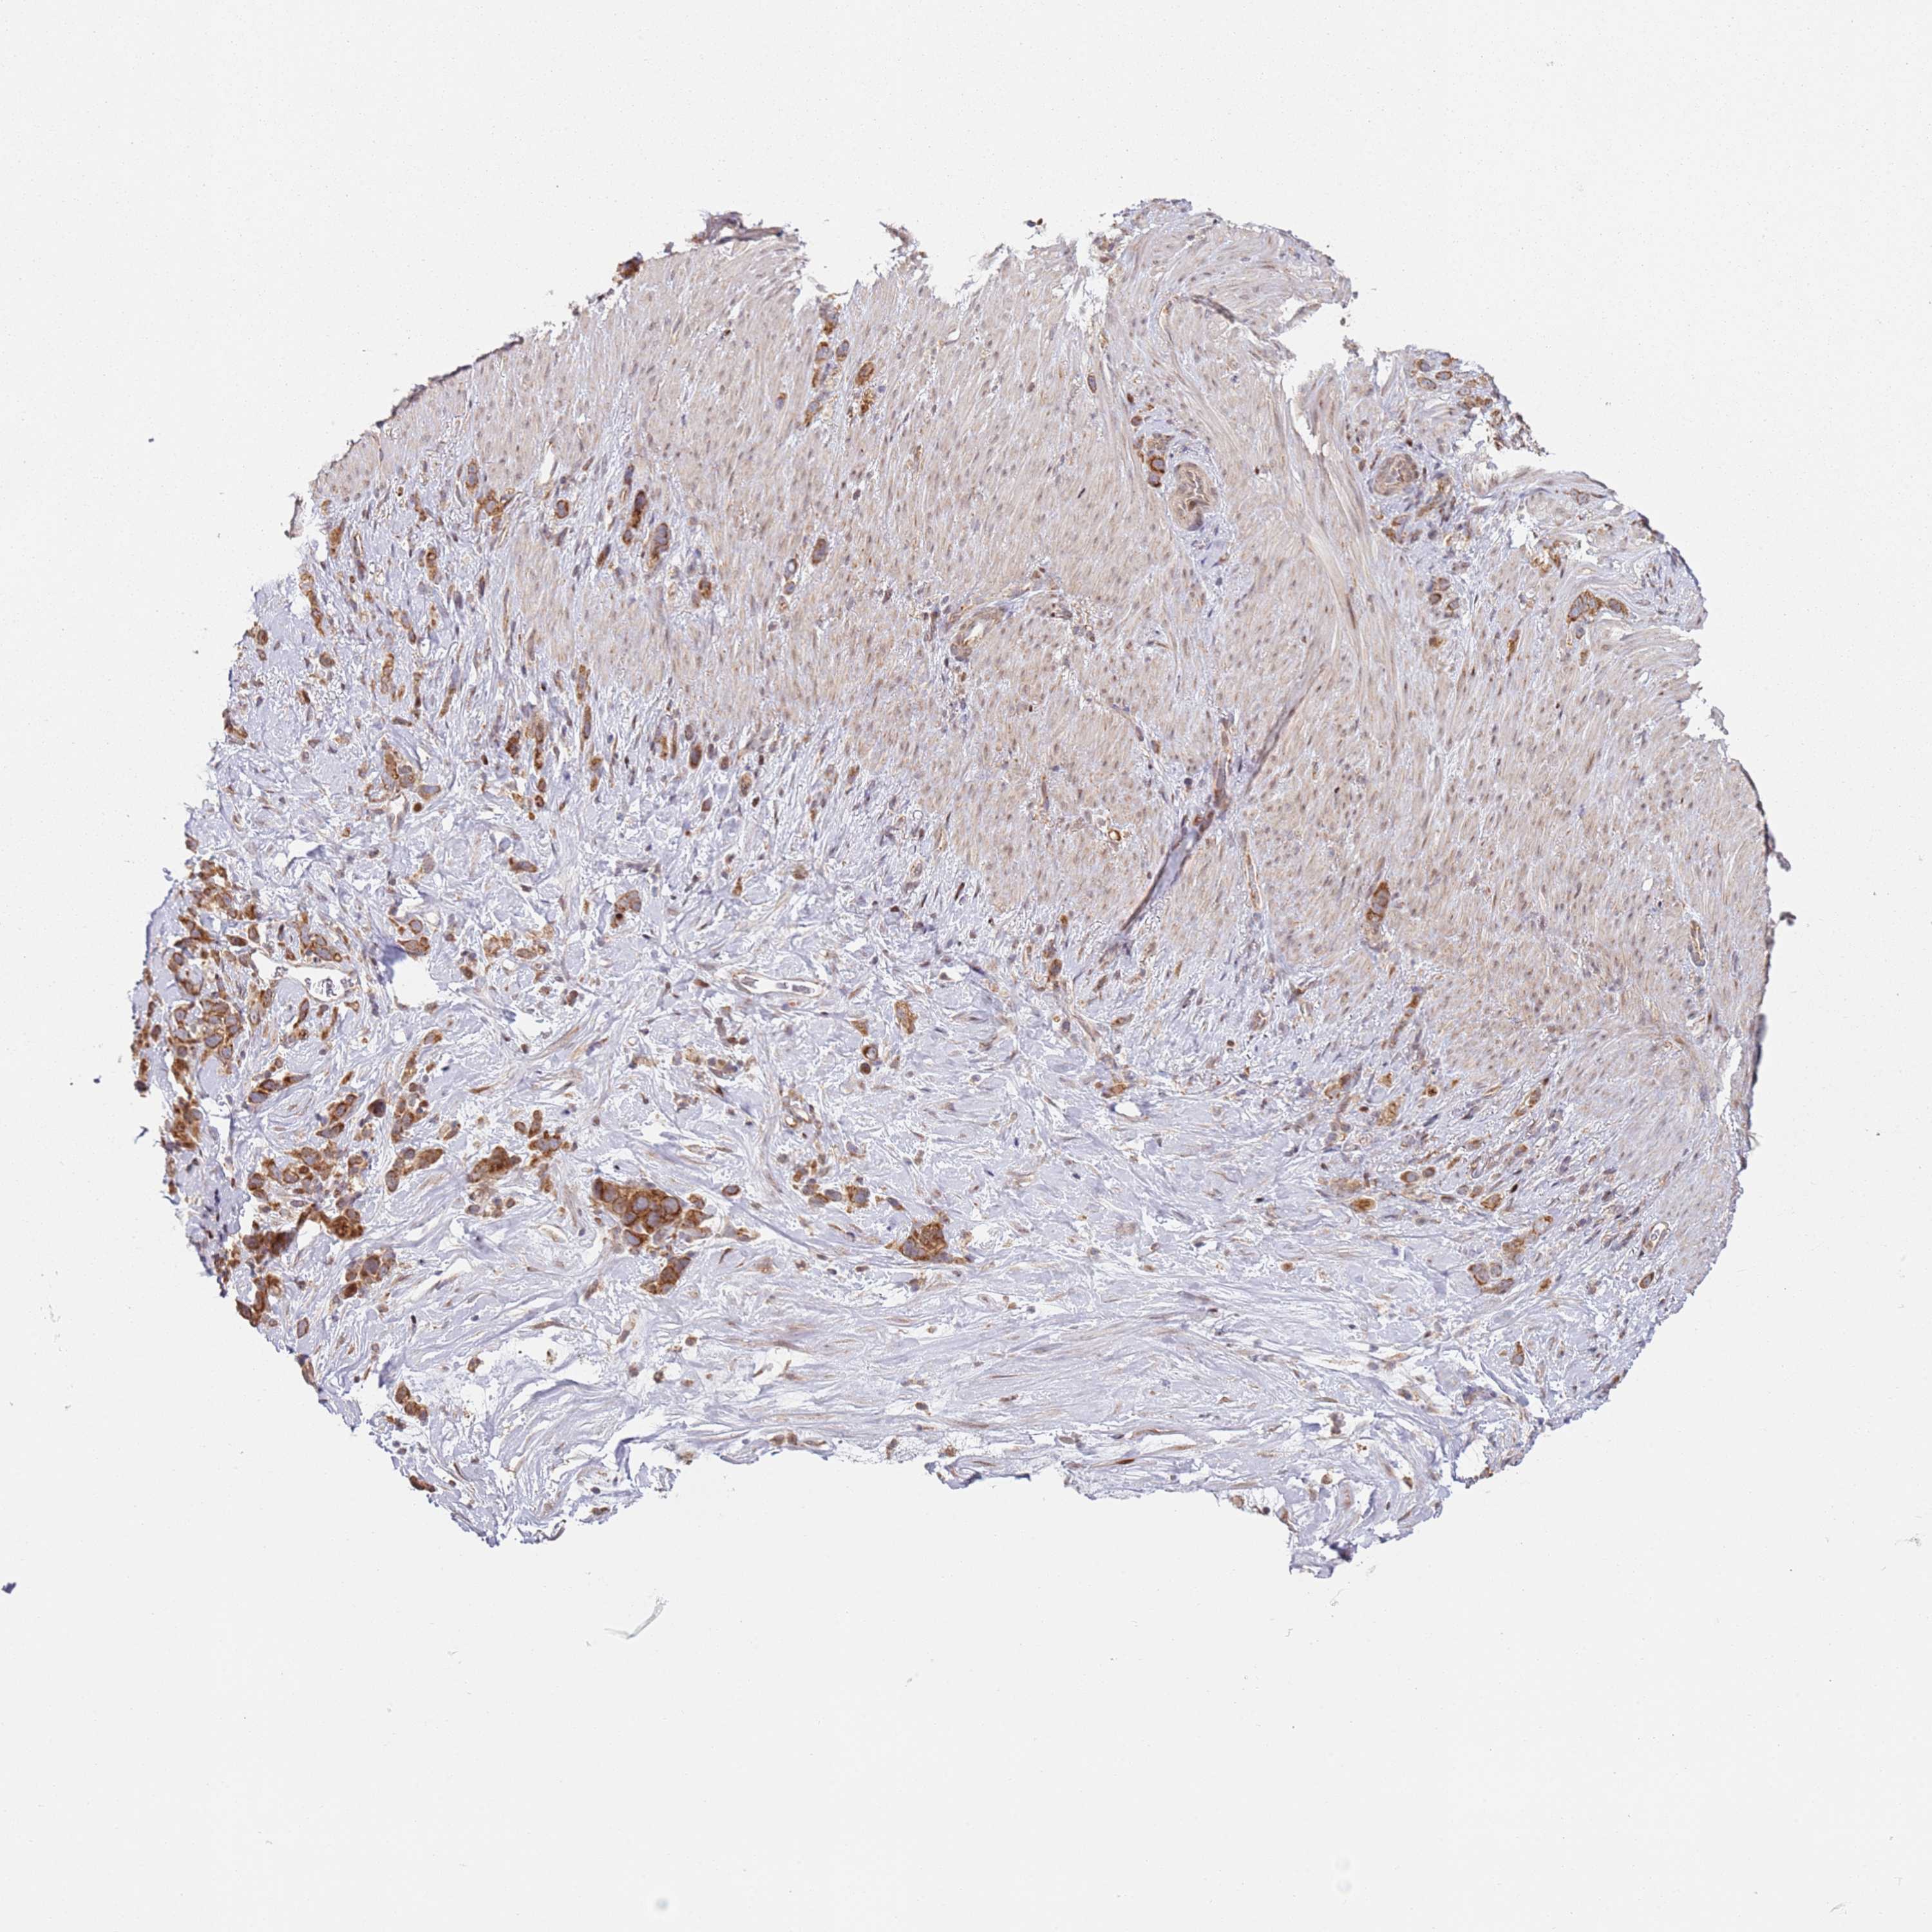

STOMACH CANCER - Protein expressioni

A mouse-over function shows sample information and annotation data. Click on an image to view it in a full screen mode. Samples can be filtered based on level of antibody staining by selecting one or several of the following categories: high, medium, low and not detected. The assay and annotation is described here.

Note that samples used for immunohistochemistry by the Human Protein Atlas do not correspond to samples in the TCGA dataset.

Antibody stainingi

Antibody staining in the annotated cell types in the current human tissue is reported as not detected, low, medium, or high, based on conventional immunohistochemistry profiling in selected tissues. This score is based on the combination of the staining intensity and fraction of stained cells.

Each image is clickable and will lead to virtual microscopy that enables deeper exploration of all samples and also displays staining intensity scores, fraction scores and subcellular localization as well as patient and tissue information for each sample.

Antibody HPA046084

Staining

High

Medium

Low

Not detected

Intensity

Strong

Moderate

Weak

Negative

Quantity

>75%

75%-25%

<25%

None

Location

Nuclear

Cytoplasmic/membranous

Cytoplasmic/membranous,nuclear

Adenocarcinoma, NOS